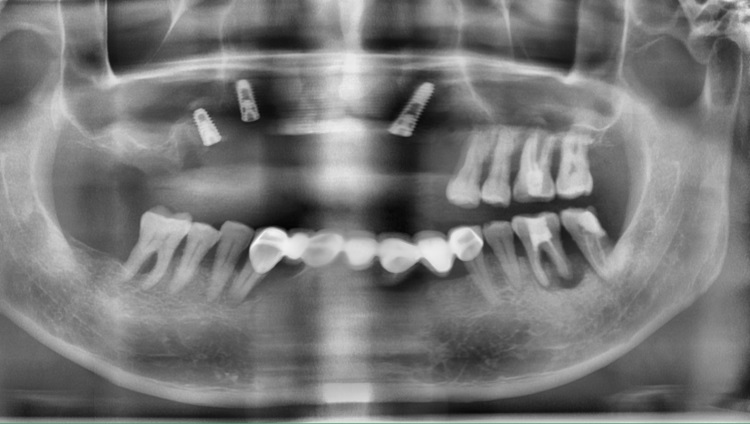

抱着了解的心态咨询种植,吴阿姨便被穗华口腔医院医生周到的服务和专业态度所感染,从口腔全景片和口内实拍图片可以看到,上颌已经没有任何牙齿,余牙松动严重,牙龈因长期戴活动假牙也是萎缩严重。

穗华口腔医院专家基于吴阿姨的情况制定了详细方案,建议先拔除残根,做2-3次牙周治疗,再利用all-on-4种植技术分散种植牙咀嚼强度,借助数字化精准种植动态导航系统精准定位手术区域,“创口米粒大小简直不可思议”。术后影像显示,植体植入位置与计划位置基本吻合。护士还向吴阿姨详细讲解了术后的注意事项,“很贴心、很温暖”。